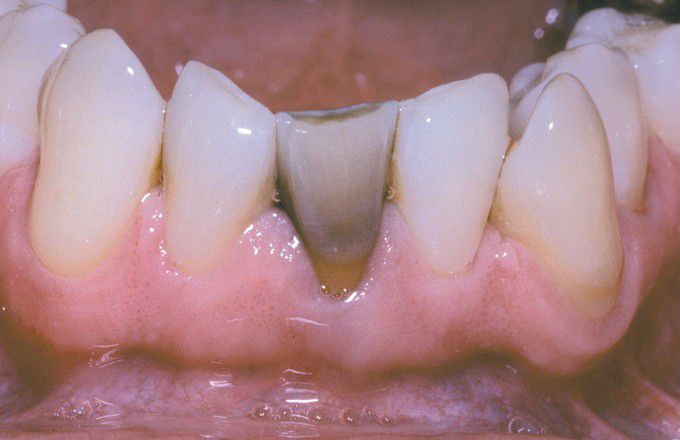

Amalgam discolouration

Green-gray discoloration of mandibular central incisor, which had endodontic access preparation restored with amalgam